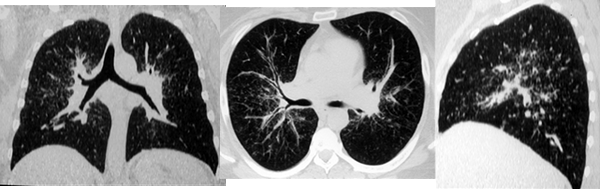

Одним из наиболее часто наблюдаемых нами при КТ признаков саркоидоза являлся симптом диссеминации (70-80% случаев). При этом превалировала картина интерстициальных изменений с ретикуло-нодулярными фокусами размерами около 1-2 мм. Распределение теней было, главным образом, перилимфатическим с локализацией в средних и верхних легочных зонах (рис. 3). Реже визуализировались гроздевидные очаги округлой или неправильной формы до 6 мм в диаметре, с преимущественно субплевральной локализацией.

Рис. 3. На РК-томограммах больной Ж., 49 лет, определяется двухсторонняя диссеминация с преимущественной локализацией в среднем легочном поясе